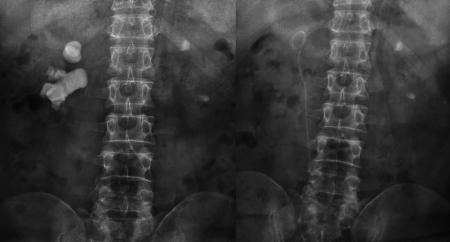

宋先生術(shù)前與第二次術(shù)后的結(jié)石對(duì)比“我兩個(gè)腎臟都長(zhǎng)結(jié)石,到現(xiàn)在已經(jīng)長(zhǎng)了30年了。自從2000年做了開(kāi)刀取石后,前前后后做了100多次體外碎石,結(jié)石還是瘋長(zhǎng)不停。”近日,在四川結(jié)石病醫(yī)院泌尿外科病區(qū),來(lái)自四川沐川縣的宋先生告訴記者,他的腎臟不知怎么回事,每隔個(gè)一兩年就長(zhǎng)出體積駭人的“巨大”結(jié)石。

又進(jìn)行了20多次體外碎石后,腎結(jié)石非但沒(méi)打掉,反而長(zhǎng)到了駭人的8公分:X光片里面形似一顆“老姜”,幾乎塞滿了右腎內(nèi)的大小通道。

“泌尿道梗阻;右腎多發(fā)結(jié)石、中度擴(kuò)張積水;左腎結(jié)石伴左腎積水,左腎縮小。”醫(yī)院的檢查結(jié)果顯示,結(jié)石充滿了宋先生的右腎,右腎功能受結(jié)石和積水的影響,僅剩4成左右,而左腎則出現(xiàn)了可怕的腎萎縮。而這些正是在宋先生接受了驚人的100多次體外沖擊波碎石,累計(jì)花掉20多萬(wàn)元后,付出的沉重代價(jià)。

“人的腎臟約長(zhǎng)10-12厘米,普通人兩、三厘米的結(jié)石,就算比較大的了,而宋先生的腎結(jié)石一年多時(shí)間,就在腎臟內(nèi)迅速長(zhǎng)到8公分。如此驚人的生長(zhǎng)速度,在臨床上十分罕見(jiàn)。”宋先生的主刀專家、四川結(jié)石病醫(yī)院泌尿一科易成然主任介紹。

在經(jīng)歷了兩次微創(chuàng)經(jīng)皮腎鏡碎石取石手術(shù)后,宋先生右腎內(nèi)的巨大結(jié)石被粉碎并清除,解除了尿路的梗阻,腎臟的積水隨之消退。目前,宋先生即將康復(fù)出院。